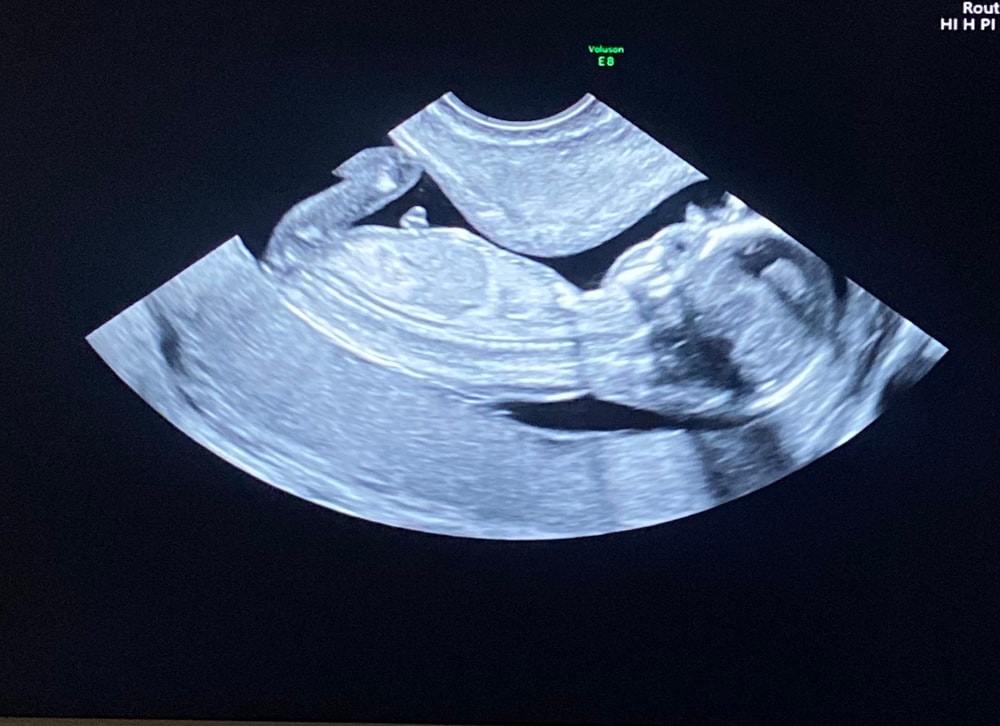

Определение Пола на 16 неделе

Знаю, что для определения Пола ещё рановато, но мне не дает покоя мой скрининг, рассматриваю его каждый день и думаю кто у нас будет, мальчик или девочка.

Знающие девочки, ваши предположения?)